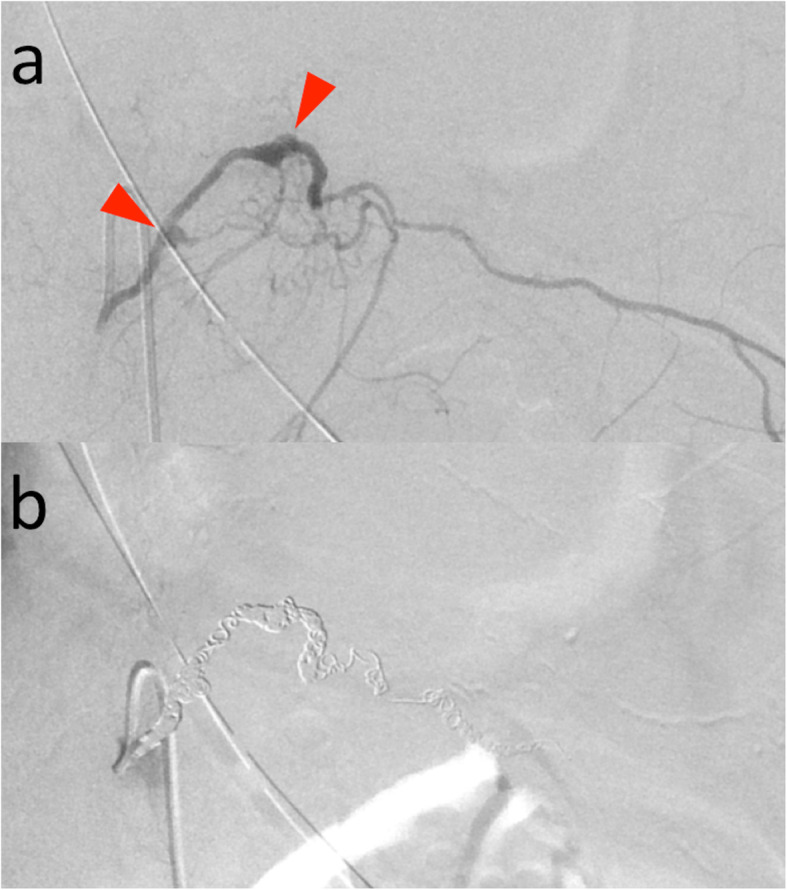

Selective angiography revealed irregular vessels and small aneurysms of the left 10th intercostal artery (Fig. 3a). Extravasation of contrast agent could not be detected. Therefore, we embolized the irregularly shaped portion of the artery. The distal site was embolized using 20 micro coils: 6 Orbit Galaxy (Codman & Shurtleff, Raynham, MA), 6 Tornado Embolization Coils (Cook Medical, Bloomington, IN), 6 Azur Embolization System CX18 (MicroVention Inc., Aliso Viejo, CA), and 2 Interlocking Detachable Coils (Boston Scientific Corporation, Marlborough, MA). The proximal site was occluded using 3 Orbit Galaxy Microcoils. The artery and aneurysms were all embolized successfully (Fig. 3b). The duration from hospitalization to completion of treatment was about 5 h.

Fig. 3.

a Selective left 10th intercostal arteriography demonstrated irregular vessels and small aneurysms (red arrows). Extravasation of contrast agent was not detected. b Left 10th intercostal arteriography after coil embolization showed complete occlusion of the aneurysms